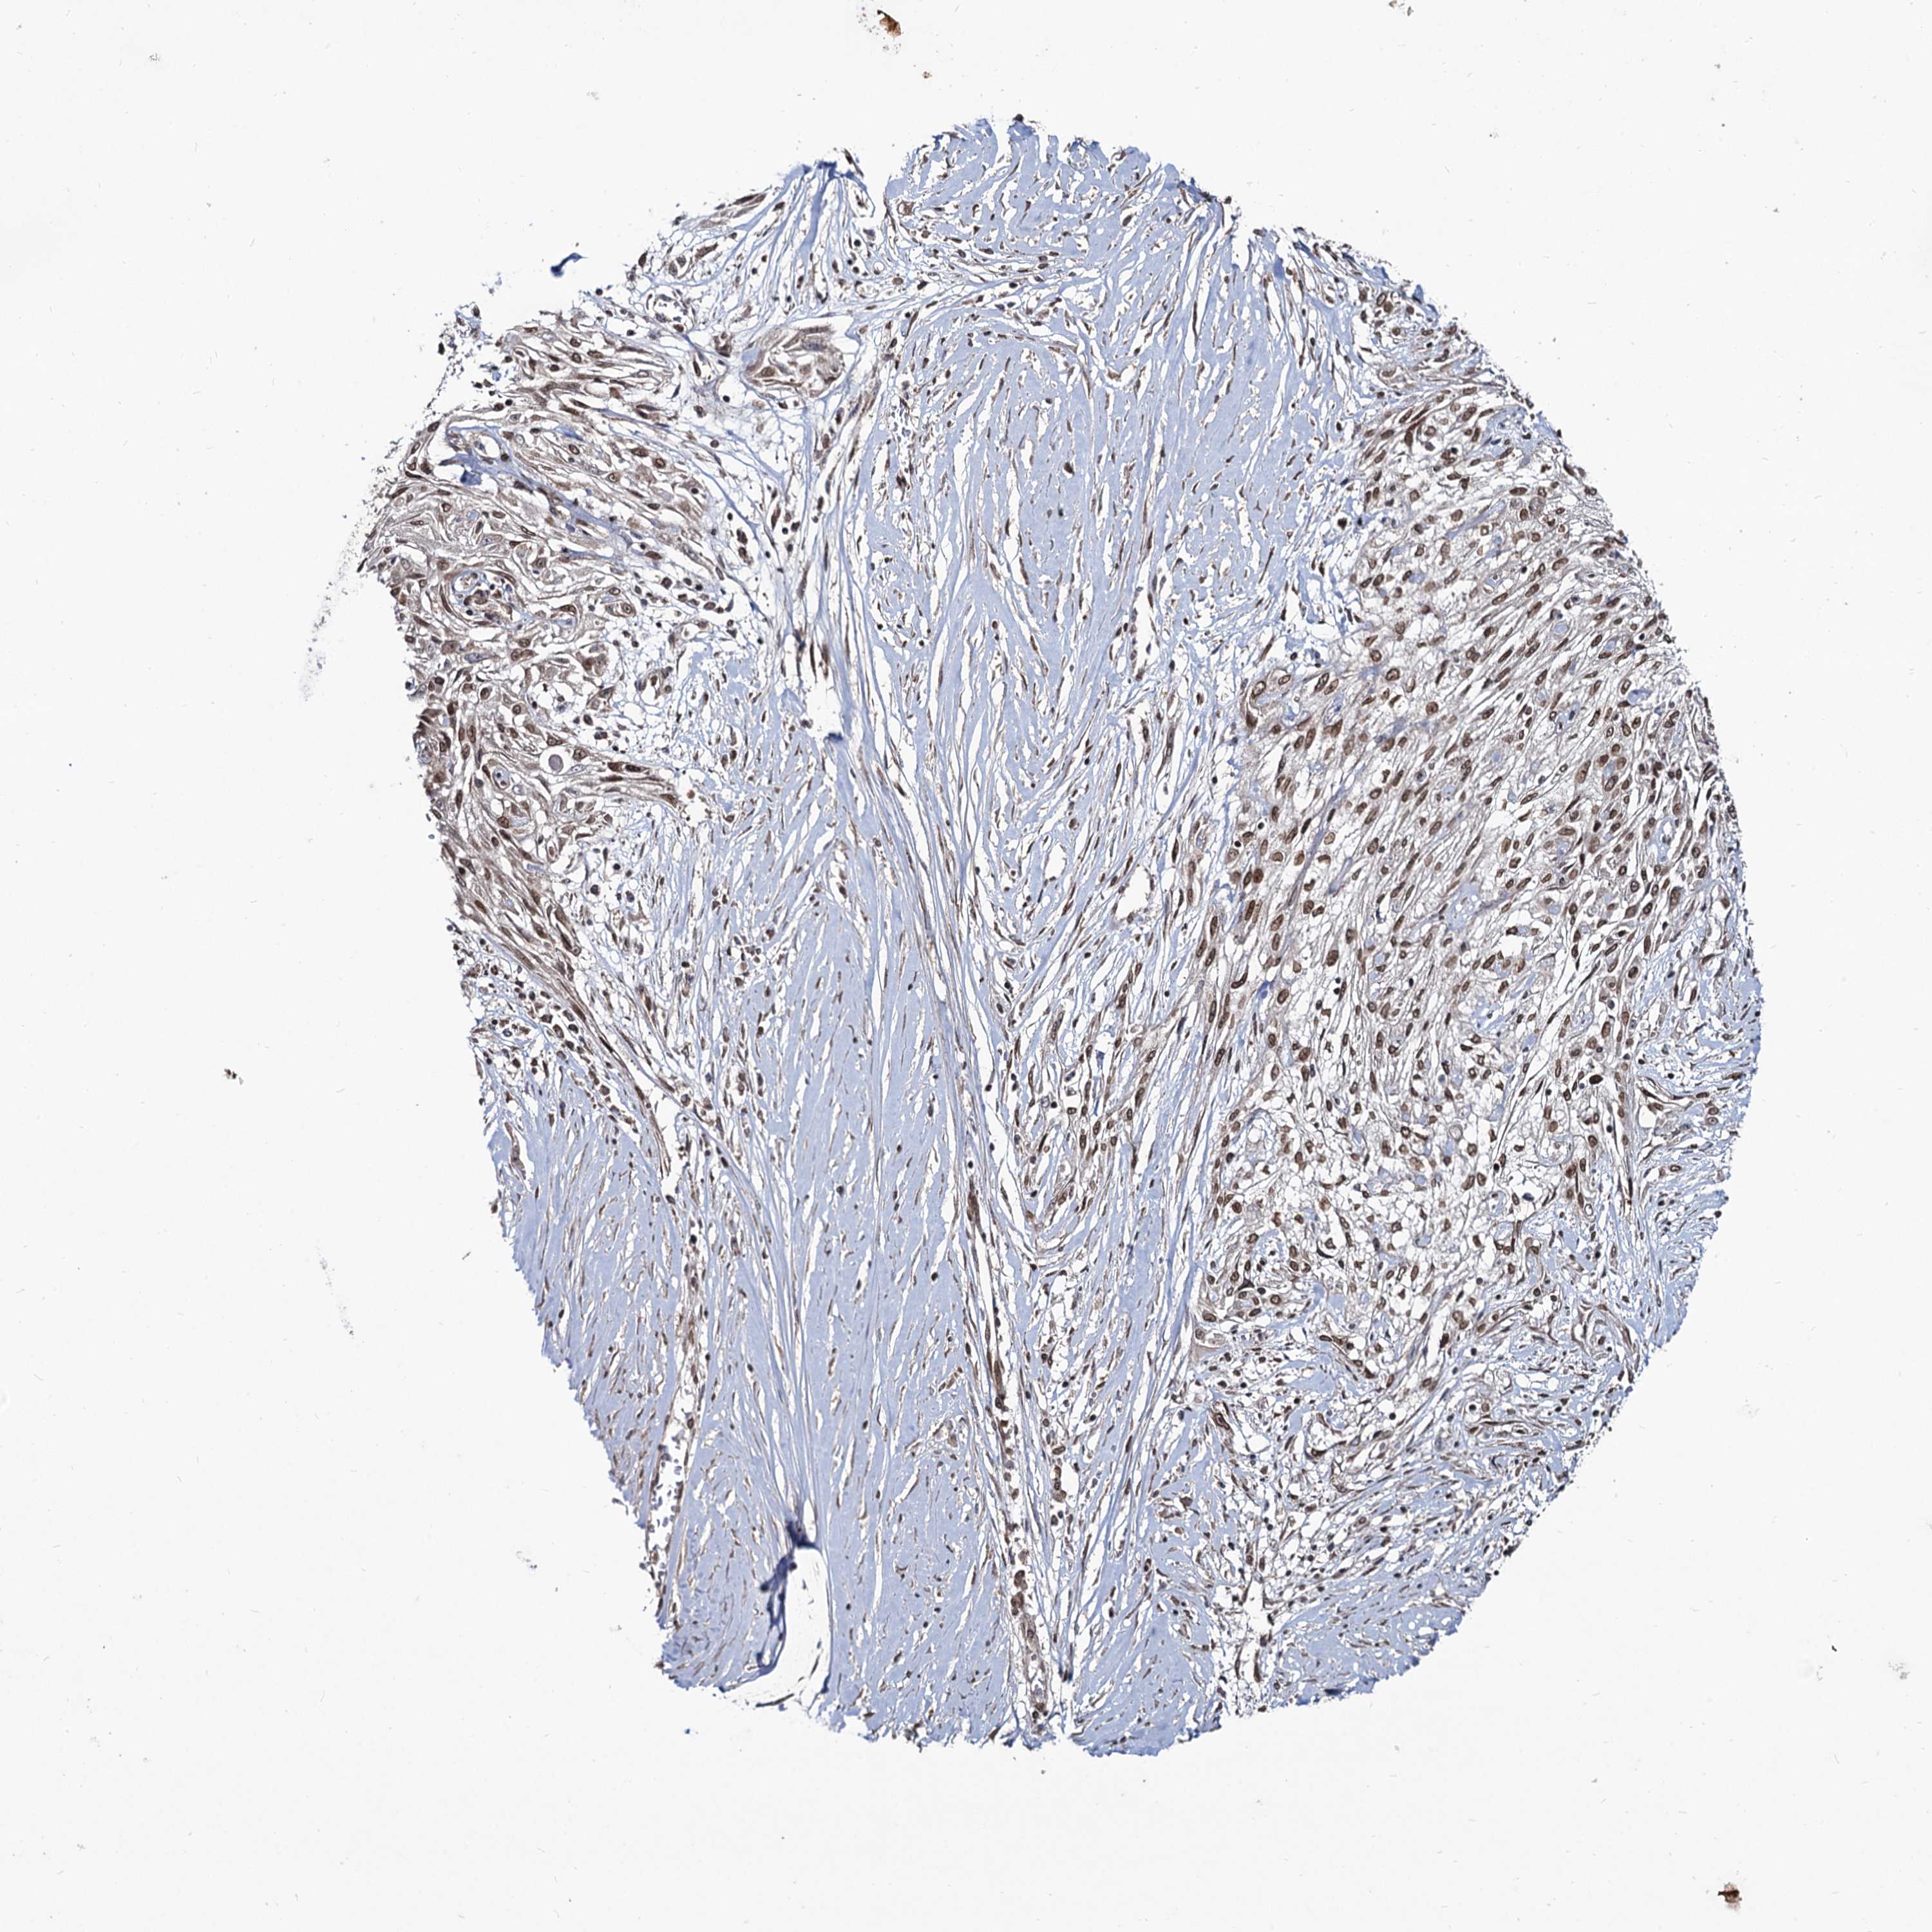

Basal cell and squamous cell cancer

SKIN CANCER - Protein expressioni

A mouse-over function shows sample information and annotation data. Click on an image to view it in a full screen mode. Samples can be filtered based on level of antibody staining by selecting one or several of the following categories: high, medium, low and not detected. The assay and annotation is described here.

Antibody stainingi

Antibody staining in the annotated cell types in the current human tissue is reported as not detected, low, medium, or high, based on conventional immunohistochemistry profiling in selected tissues. This score is based on the combination of the staining intensity and fraction of stained cells.

Each image is clickable and will lead to virtual microscopy that enables deeper exploration of all samples and also displays staining intensity scores, fraction scores and subcellular localization as well as patient and tissue information for each sample.

Antibody HPA039343

Antibody HPA040048

Squamous cell carcinoma, metastatic, NOS